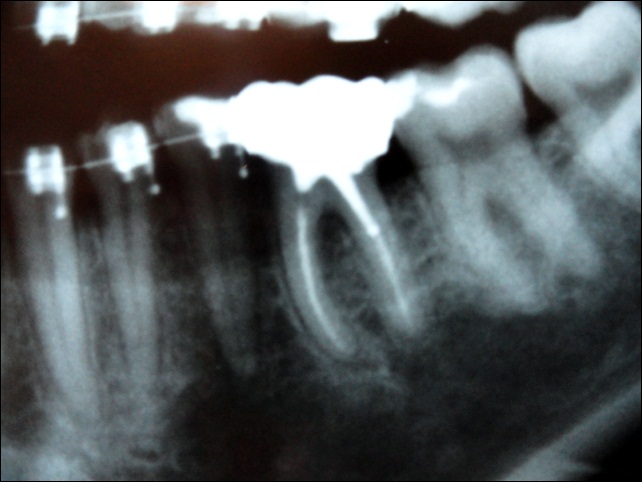

Uma BROCA, não sei afirmar, ao certo, a marca comercial, esférica (uma 1012, 1013???).

Um certo dia, a Broca encontrou o BROCO (ou melhor, o BLOCO) e, numa paixão arrebatadora, contando com o empenho do cupido “Corega Lambão”, fundiram-se…

(Caso ocorrido na clínica onde trabalho, gentilmente cedido pela Dra. Carolina Cunha)